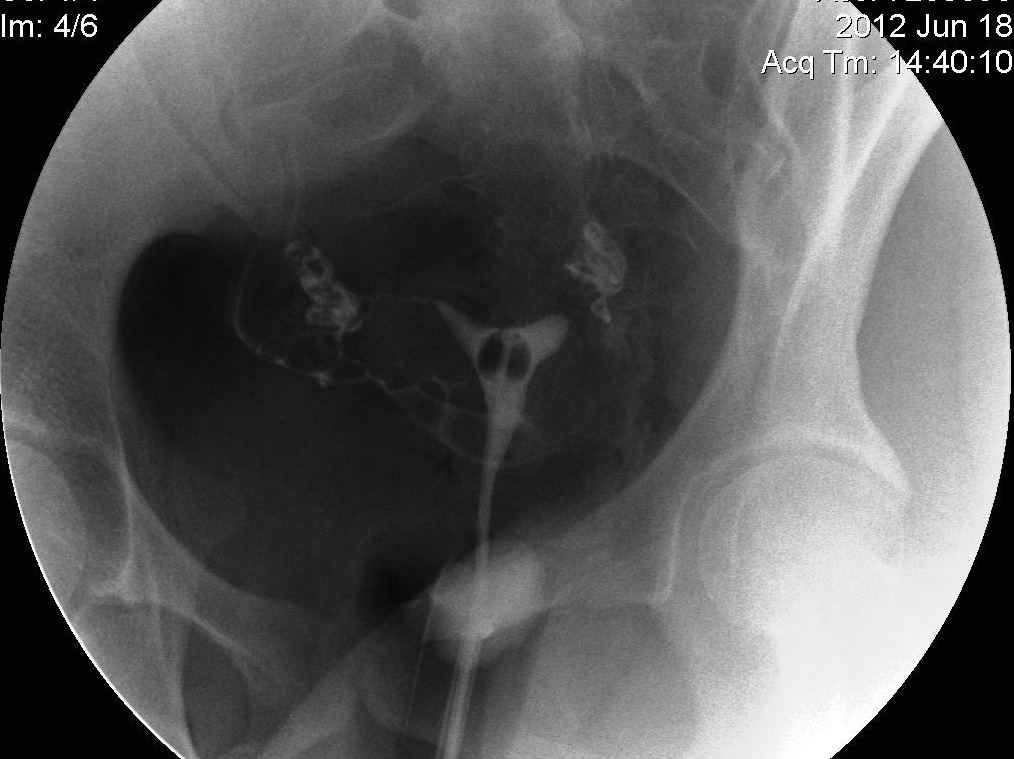

Hysterosalpingogram (HSG) test for Fallopian Tubes Dye Test In Fallopian Tubes A hysterosalpingogram (hsg) is a test that checks a woman’s uterus and fallopian tubes for any blockages or scarring that could prevent conception. It can help diagnose infertility and. Dye Test In Fallopian Tubes.

Hysterosalpingography (HSG), also known as uterosalpingography, is a Dye Test In Fallopian Tubes It can help diagnose infertility and. A hysterosalpingogram (hsg) is a test that checks a woman’s uterus and fallopian tubes for any blockages or scarring that could prevent conception. Dye Test In Fallopian Tubes.